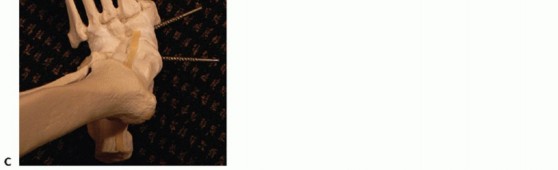

The two most common methods of internal fixation currently employed are large beaming intramedullary screws or rigid medial plate and screw constructs (FIG 7).22,25

--- FIG 7 • A,B. Preoperative weight-bearing radiographs on a 57-year-old diabetic female with no open wounds. She underwent correction of the deformity followed by internal fixation with super construct beaming screws.

FIG 7 • (continued) C,D. Radiographs at 1 year, demonstrating successful union.*

Internal fixation can be achieved with either intramedullary screws or a large medial screw-plate construct.

Beaming is accomplished by passing large intramedullary screws from the metatarsophalangeal joints of the first and fourth metatarsals across the osteotomy and into the talus. This superstructure concept theoretically behaves much like an intramedullary nail.

Several device manufacturers have developed large medial plates that can be used with “osteoporosis” large threaded screws to optimize stabilization in this patient population with poor bone quality.22,25 -